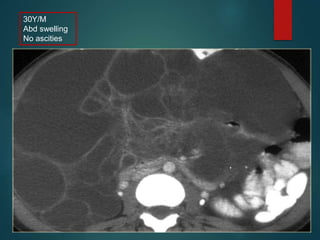

Mesenteric cyst..

• Usually it is a lymphangioma.

• Other… enteric duplication cyst, enteric cyst,

nonpancreatic pseudocyst and mesothelial cyst are very

uncommon and have no specific features.

• Lymphangioma is a benign lesion of vascular origin.

• Most lymphangiomas are located in the neck, but 5% of

lymphangiomas are abdominal.

• Lymphangioma has enhancing septa.

• No ascities

30Y/M

Abd swelling

No ascities

Mesenteric cyst.. • Usuallyit is a lymphangioma. • Other… enteric duplication cyst, enteric cyst, nonpancreatic pseudocyst and mesothelial cyst are very uncommon and have no specific features. • Lymphangioma is a benign lesion of vascular origin. • Most lymphangiomas are located in the neck, but 5% of lymphangiomas are abdominal. • Lymphangioma has enhancing septa. • No ascities

• #14 Mesenteric cyst is a descriptive term for any cystic lesion within the mesentery. According to origin it is…lymphangioma,mesothelioma,enteric,nonpan psudocyst(inf/trauma),cystic teratoma. Unlike in cystic peritoneal metastases, ascites is not a feature of lymphangioma. you see a septated cystic lesion without ascites the most likely diagnosis is a lymphangioma